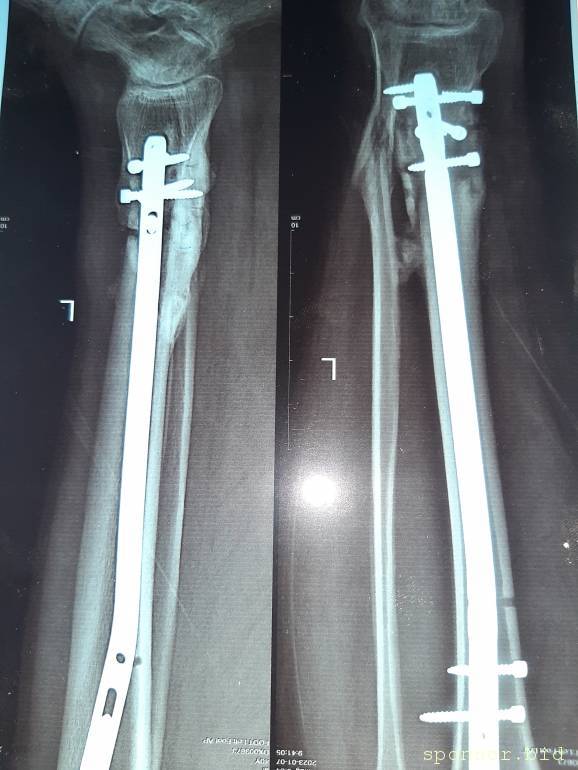

Вот что со мной произошло: летом прошлого 2022 года я неудачно упал, и сломал левую ногу, да так, что всё не закончлось просто гипсом. Перелом был сложным, пришлось делать операцию, ставить биос. Операция прошла с осложнениями, был свищ, нога после операции долго не заживала. Потом сломался крепёжный саморез, стало ещё хуже. Заболела правая нога в колене и бёдре. На приёме у врача сказали нужна операция! И в ближайшее время! Но я на больничном уже целый год, и после такого продолжительного лечения, все мои финансы на нуле. Ходить не могу, спать не могу, мучают постоянные боли. У меня развился сахарный диабет, ноги болят, появилась венозная недостаточность и варикоз. Мне всего 41 год. Получается я останусь инвалидом навсегда... Но у меня есть двое детей 5 и 14 лет... В данный момент я не могу встать на ноги из-за отсутствия финансовых средств. Моя мама Лариса Андреевна, помогает мне по мере своих сил. Ей приходится работать на производстве. Но ей уже 75 лет...

Нужна помощь сыну сотрудницы Не может ходить. - 20230719_135246.jpg

Нужна помощь сыну сотрудницы Не может ходить. - 20230719_135256.jpg

Нужна помощь сыну сотрудницы Не может ходить. - 20230719_135335.jpg

Нужна помощь сыну сотрудницы Не может ходить. - 20230719_135402.jpg

Нужна помощь сыну сотрудницы Не может ходить. - 20230719_135435.jpg

Нужна помощь сыну сотрудницы Не может ходить. - 20230719_135445.jpg

Нужна помощь сыну сотрудницы Не может ходить. - 20230719_135457.jpg